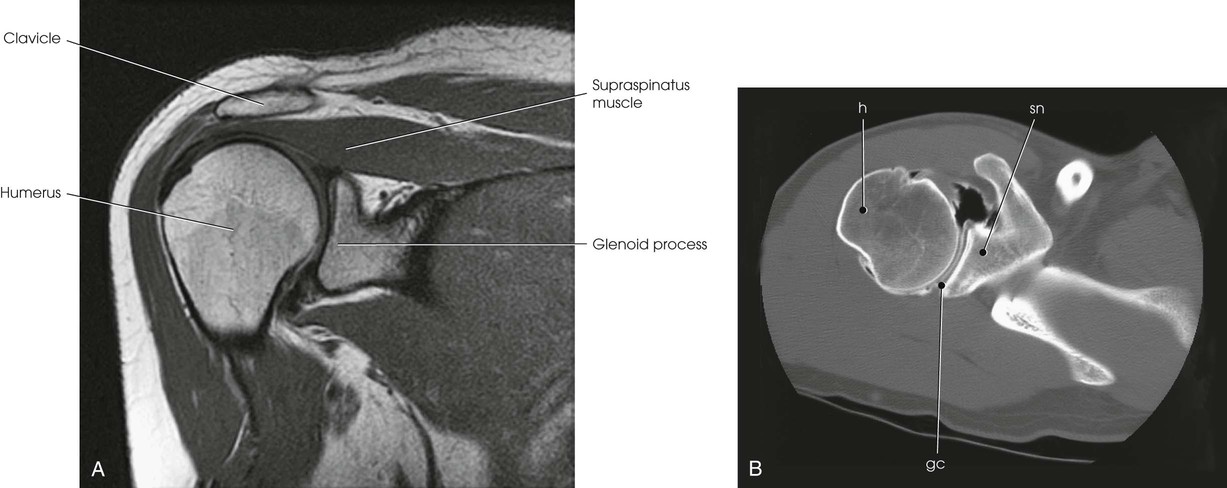

The scapulohumeral articulation between the glenoid cavity and the head of the humerus forms a synovial ball-and-socket joint, allowing movement in all directions (Figs. 5-9 and 5-10). This joint is often referred to as the glenohumeral joint. Although many muscles connect with, support, and enter into the function of the shoulder joint, radiographers are chiefly concerned with the insertion points of the short rotator cuff muscles (Fig. 5-11). The insertion points of these muscles—the subscapular, supraspinatus, infraspinatus, and teres minor—have already been described.

The joint space between the humeral head and the glenoid cavity (scapulohumeral or glenohumeral joint) is shown (Figs. 5-19 and 5-20).